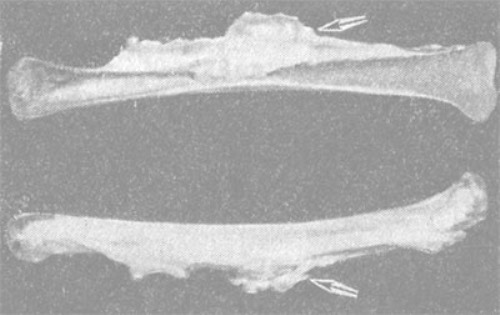

Под микроскопом процесс выглядит как уплощение кости, которое локализуется на длинных трубчатых костях (плечевой, бедренной, большеберцовой и т.п.) и как будто стекает верху вниз, образуя при этом напластования, похожие на наплывы горящей свечки.

Диагноз можно точно поставить только с помощью рентгена. На нем видны участки, на которых кость сильно уплотнена. К тому же характерна форма таких образований – «стекающая».